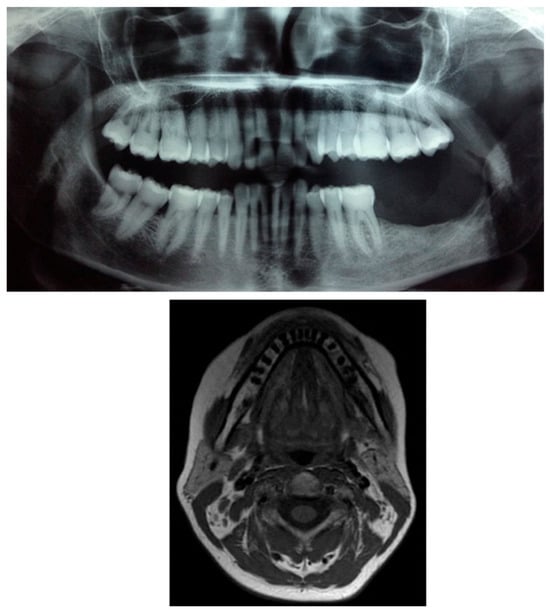

Intraoral examination revealed an exophytic erythematous lesion measuring approximately 2.5 × 2 cm on the left retromolar trigone, while orthopantomographic X-ray imaging demonstrated a corresponding radiolucency in the same region (Figure 2). Considering her systemic condition and ongoing therapy with cyclophosphamide, a multidisciplinary management plan was initiated, which included second-level imaging (MRI) to evaluate lesion extension (Figure 3), a professional oral hygiene session, chlorhexidine 0.12% mouth rinses, and selective grinding of the occlusal cusps of the involved mandibular molars to minimize traumatic contact. An incisional biopsy was then performed using a cold scalpel combined with CO2 laser, along with extraction of tooth 3.8, suspected to contribute to local trauma. Histopathological evaluation of this specimen revealed only epithelial alterations and abundant granulation tissue without evidence of neoplasia, and a definitive diagnosis could not be established at this stage (Figure 4a,b).

Figure 2.

OPG x-ray and the blue arrow show a focus of radiolucency behind the lower-left third molar.